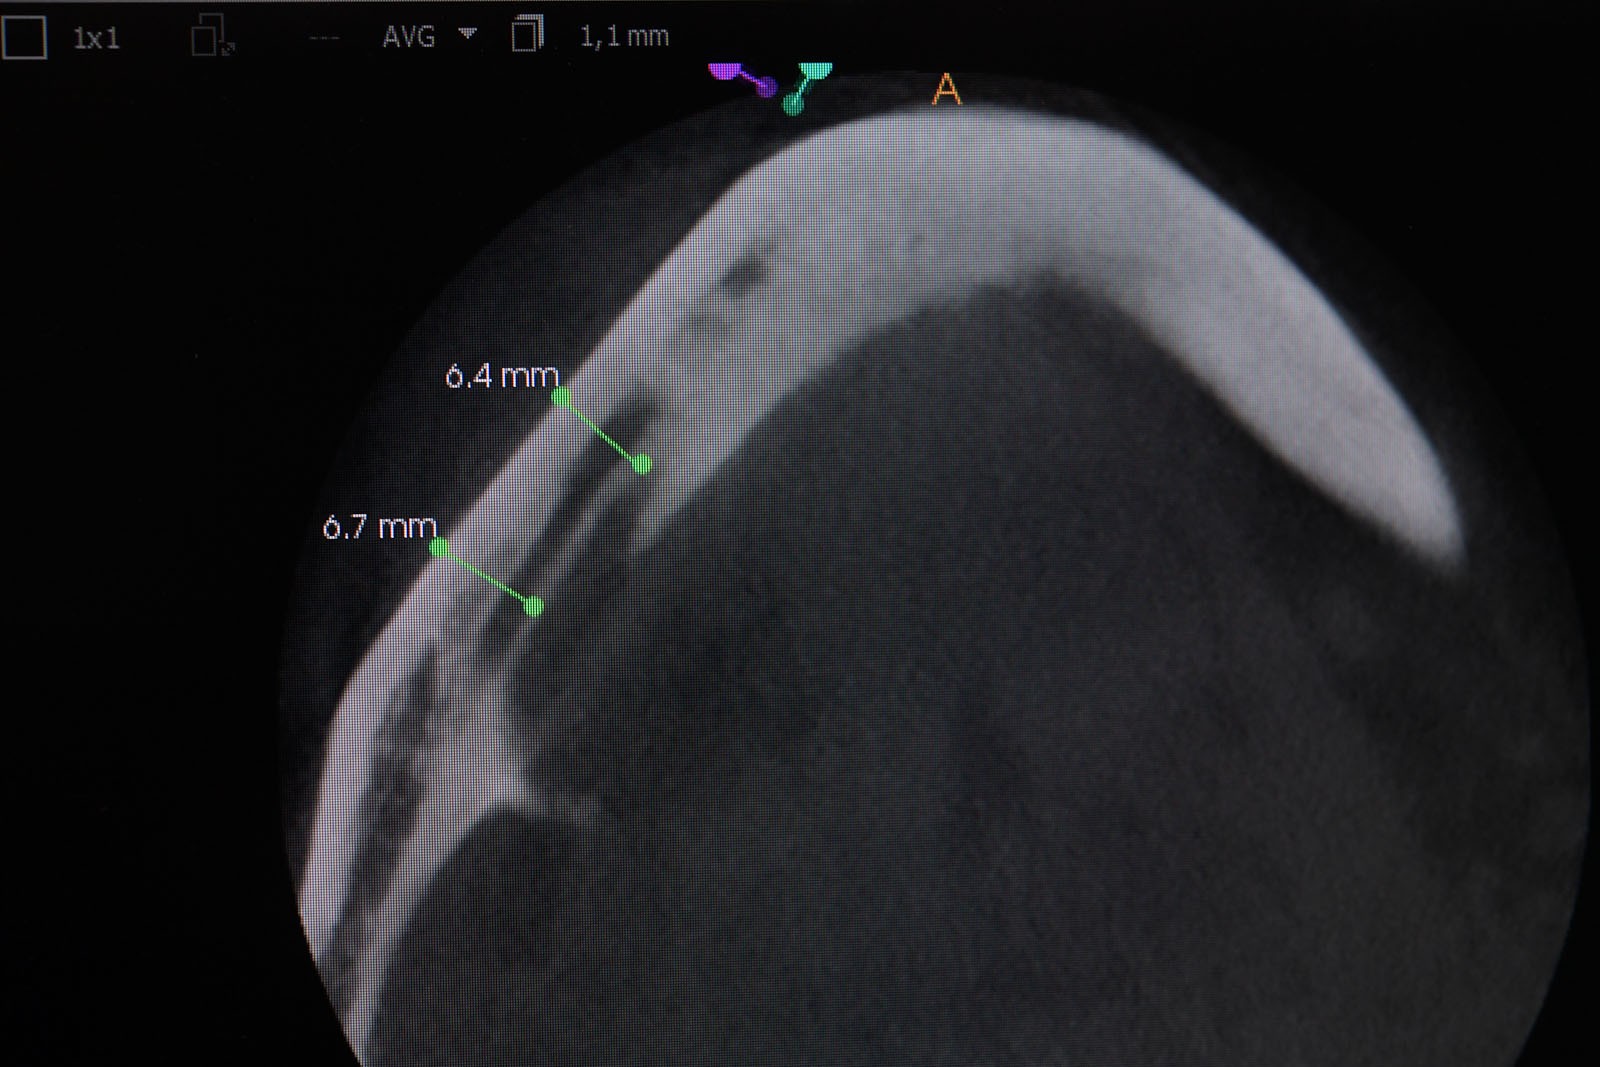

Przed podjęciem leczenia należy określić stopień zaniku kości szczęk oraz żuchwy. W tym celu przeprowadza się badanie kliniczne oraz odpowiednią diagnostykę obrazową pacjenta. Uwzględnia ona zdjęcie panoramiczne OPG jako podstawę dwuwymiarowego obrazowania podłoża kostnego oraz możliwe jest badanie tomograficzne CT lub bardziej precyzyjna tomografia stożkowa CBCT. Opcjonalnie wykorzystywana diagnostycznie tomografia pozwala na bardziej wnikliwą ocenę stopnia zaniku kości w trójwymiarowym, przestrzennym obrazie.

Precyzja projektu druku siatki bazuje na dokładności odwzorowania kształtu kości w stożkowej tomografii komputerowej CBCT, co zapewnia ich dobre przyleganie do podłoża kostnego oraz ogranicza powstawanie powikłań w postaci obnażania się siatek.